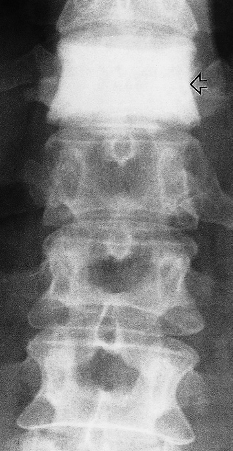

4- Haemangioma

Vertical striations are present in this normal-sized vertebra (arrowhead).